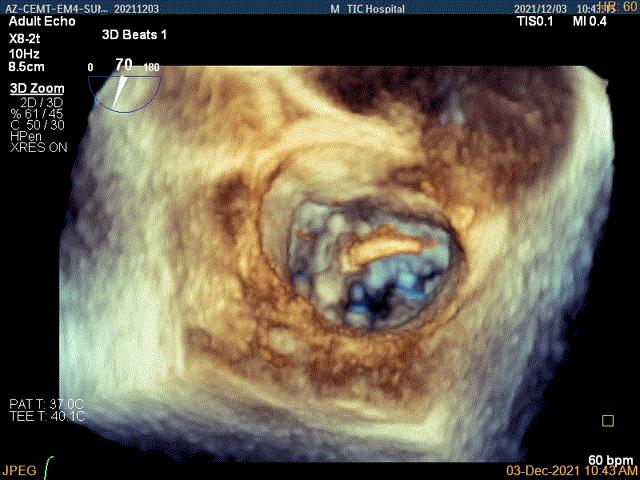

3D-color MV view:大量反流,起源于1区

3D视图菲薄的卵圆窝,穿刺点位近似于3点位

3D视图下到达目标位置

3D视图下开夹子旋转使得clip的两个arm与MV对合线垂直

3D证实夹子AC区残余脱垂被禁锢住

3D-color证实无明确残余分流